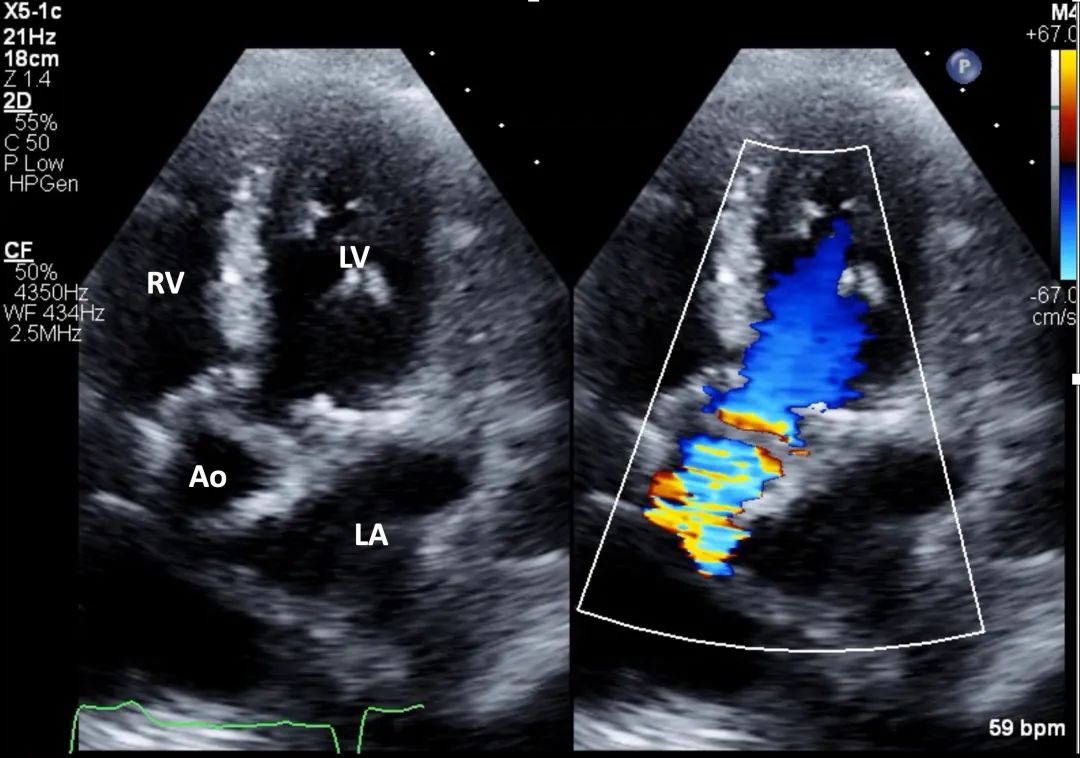

7、心尖五腔心切面: 在主动脉瓣处的彩色多普勒显示主动脉瓣狭窄引起的彩色镶嵌血流(mosaic color flow)模式,且可显示主动脉瓣反流(aortic regurgitation,AR)。应确认湍流起始位置,确保湍流源自瓣膜层面,而非瓣下(如主动脉瓣下隔膜或肥厚型心肌病所致左室流出道梗阻)或瓣上位置(图8,视频5)。

图8. 心尖五腔心切面评价主动脉瓣狭窄(有和彩色多普勒对比)

心尖五腔心切面结合主动脉瓣处彩色多普勒,用于评估流出道梗阻所致狭窄性彩色镶嵌血流模式以及主动脉瓣反流。缩写同图2。

视频5. 心尖五腔心切面应用彩色多普勒(彩色与二维灰阶对比模式),评估主动脉瓣是否存在流出道梗阻所致的狭窄性彩色镶嵌血流模式,以及主动脉瓣反流情况。